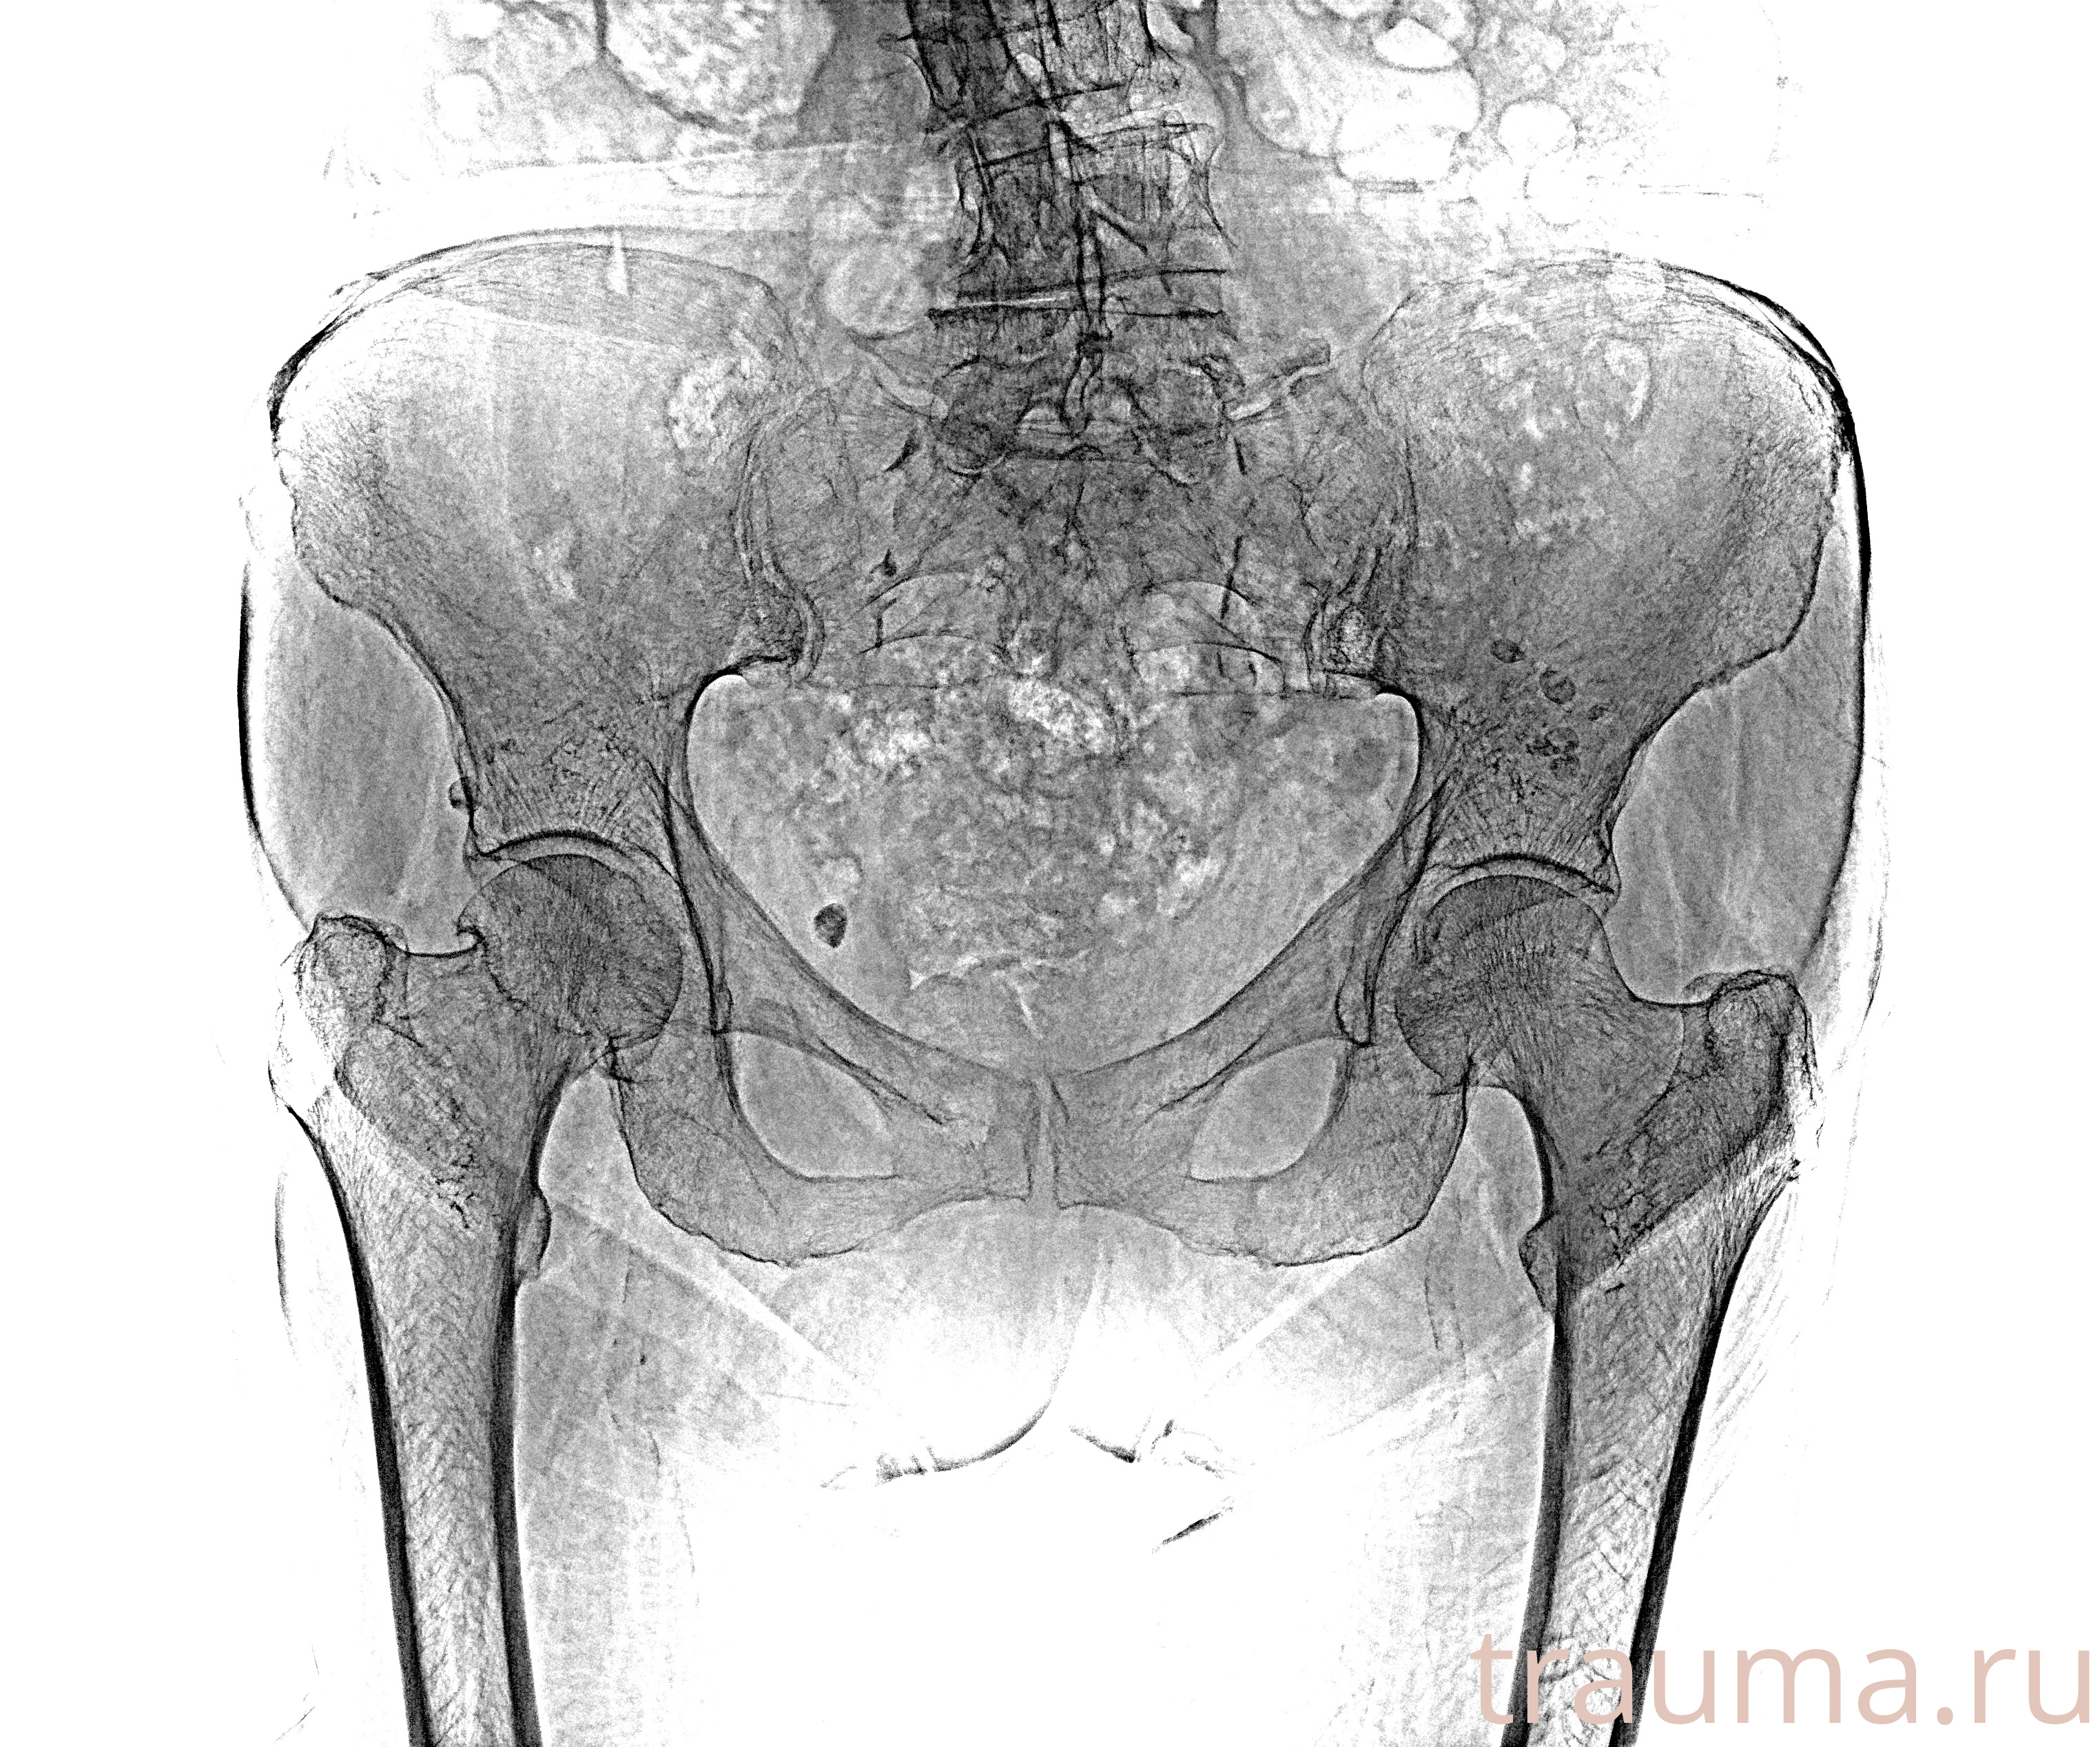

Рентгенограммы

Рентген на дому: по вашему адресу приезжает врач-рентгенолог, травматолог-ортопед с мобильным рентгеновским аппаратом, проводит диагностику травмы или заболевания, делает необходимые рентгенограммы, дает рекомендации по дальнейшему лечению. Получить качественные снимки в домашних условиях возможно благодаря уникальной методике, разработанной МосРентген Центром для института  Склифосовского

при переломе шейки бедра и пневмонии от компании МосРентген Центр - партнера Института имени Склифосовского